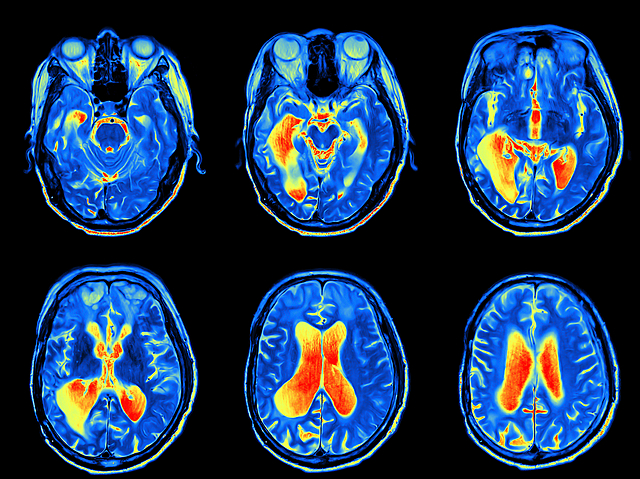

• MRI

MRI

La primera idea de crear un MRI fue por Herman Carr (un físico y pionero de las imágenes por resonancia magnética). En1972 un físico y científico llamado Raymond Davidian patentizó y creó la primera máquina de MRI. Pero no fue hasta el 1980 que se realizo la primera imagen clínicamente para observar los tejidos de un paciente.